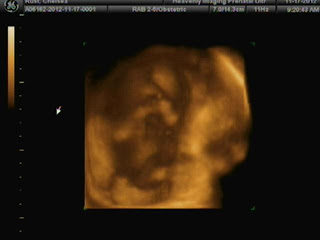

And now on to 17 weeks :)

How far along? 17 weeks 3 days

Gender: It’s a Girl!!